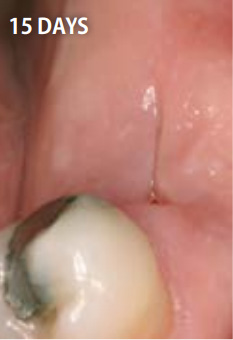

上記の写真はリッジプリザベーションにPRGFを用いたもので、非常に高い効果を得ることができます。

●PRGFを利用した場合

15日後

抜歯してできた穴にPRGFを入れると、上皮や骨の再生が促進され、短期間で抜歯窩がふさがります。また、抜歯後の痛みと腫れも軽減します。